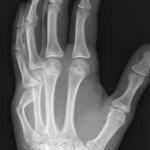

Other phalangeal fractures

Undisplaced extra-articular fractures with NO rotational deformity

- Buddy strap and resting volar slab with follow up in Plastic Surgery clinic in 1-2 days.

Displaced, angulated, intra-articular fractures or rotational deformity

- Reduce fracture under ring block +/- sedation if appropriate. Otherwise refer to the Plastic Surgery team.